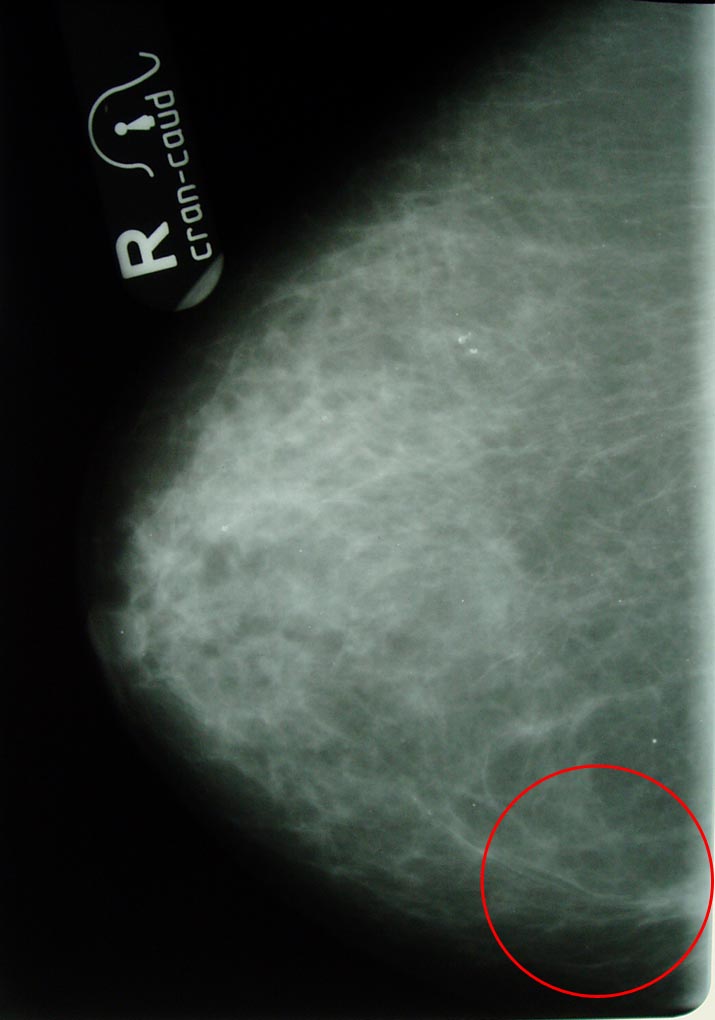

Маммограмма в динамике.

Больная раком правой молочной железы T4аN0M0. Регресс.

14.03.2006 (после 6 месяцев траволечения)